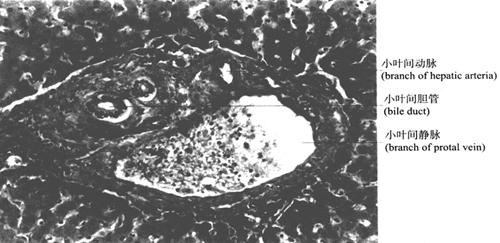

(4)肝门管区:相邻肝小叶与肝小叶之间的结缔组织,见三种管道伴行,称门管区(portal area)(图9-44)。小叶间动脉是肝动脉的分支,管径细,腔小,管壁相对较厚;小叶间静脉是门静脉的分支,管径大,腔大而不规则,管壁薄;小叶间胆管是肝管的分支,管壁为单层立方上皮。

图9-44 肝门管区(400×)